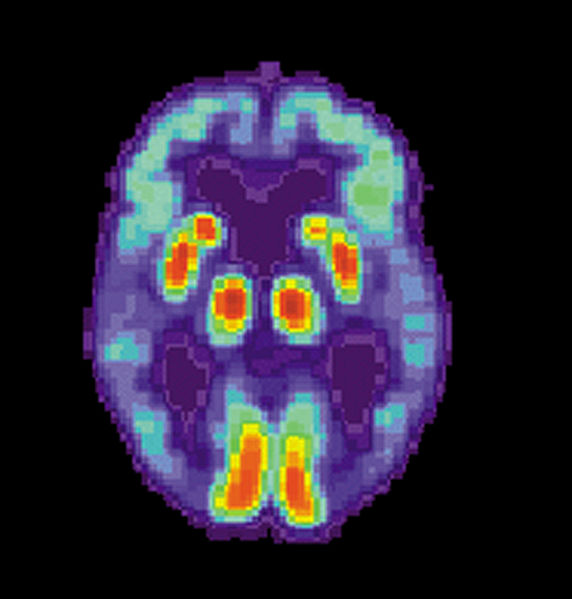

Our knowledge of the human brain is still fairly limited, therefore we do not really know what actually happens in the brain to cause depression. It is likely that with most instances of clinical depression, neurotransmitter function is disrupted. Neurotransmitters are chemicals that carry signals from one part of the brain to the next. There are many neurotransmitters, serving different purposes, however three important ones that affect a person’s mood are serotonin, noradrenaline and dopamine.

In normal brain function, neurotransmitters jump from one nerve cell to the next, with the signal being as strong in the second and subsequent cells as it was in the first. However, in people who are depressed, the mood regulating neurotransmitters fail to function normally, so that the signal is either depleted or disrupted before passing to the next nerve cell.

In non-melancholic depression, it is likely that the transmission of serotonin is reduced or less active, whereas in people with melancholic and psychotic depression, the neurotransmitters noradrenaline and dopamine are more likely to have failed or be functioning abnormally.